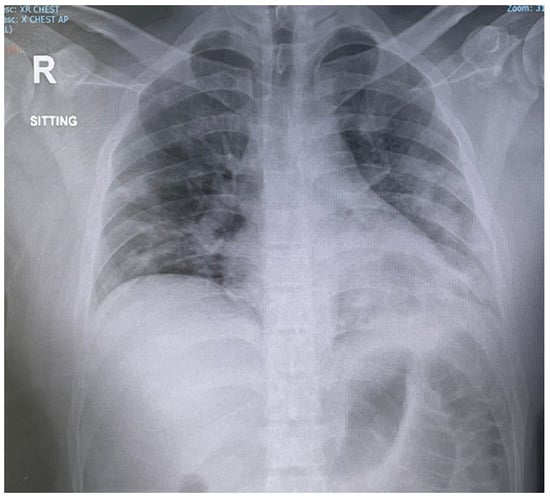

Rapid Clinical and Radiological Improvement in a Patient with Severe COVID-19 Infection Treated with Convalescent Plasma

2. Case Report